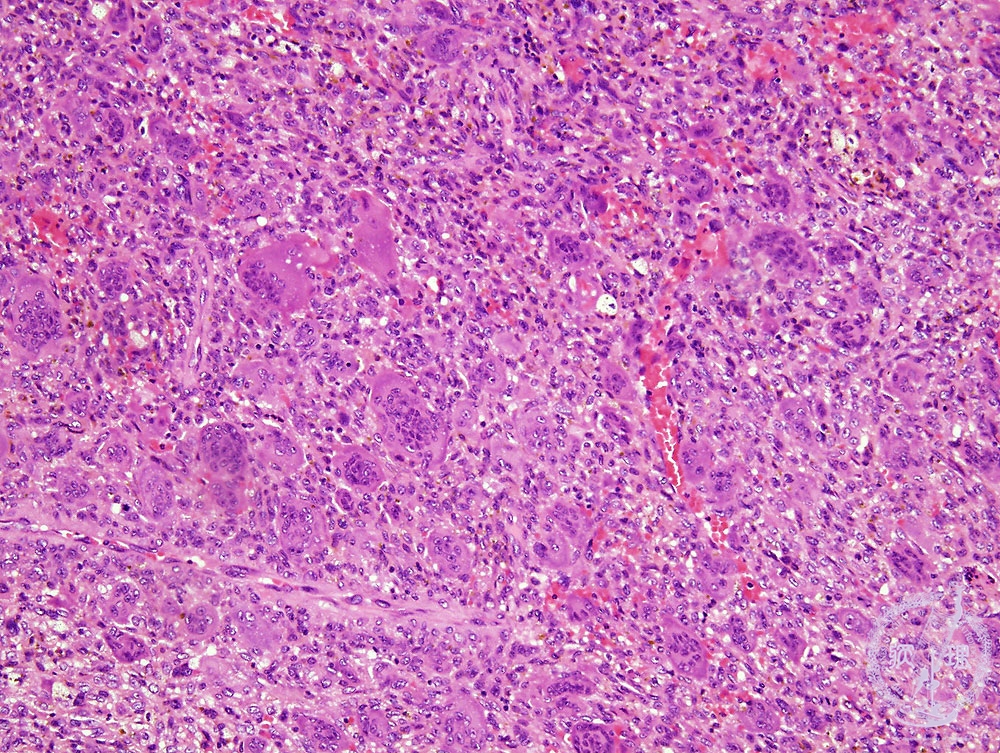

Microscopic view (HE; middle power view): Proliferation of the mixture of mononuclear and multinuclear cells.